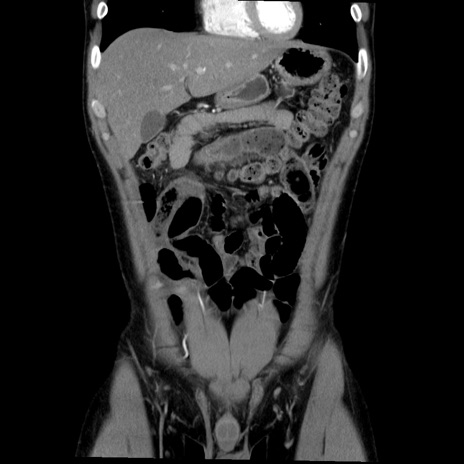

症例36(冠状断像)

【症例】20歳代 男性

【主訴】心窩部痛

【現病歴】今朝より上腹部痛あり。一旦軽快していたが再度出現したため救急要請。昨日夕に白身の魚を含む刺身を食べた。

【身体所見】BP 136/89mmHg、HR 74/min、BT 37.0℃、腹部:膨満、軟、心窩部に圧痛あり。反跳痛なし、筋性防御なし、腸雑音やや亢進あり。

【データ】WBC 17700、CRP 0.48